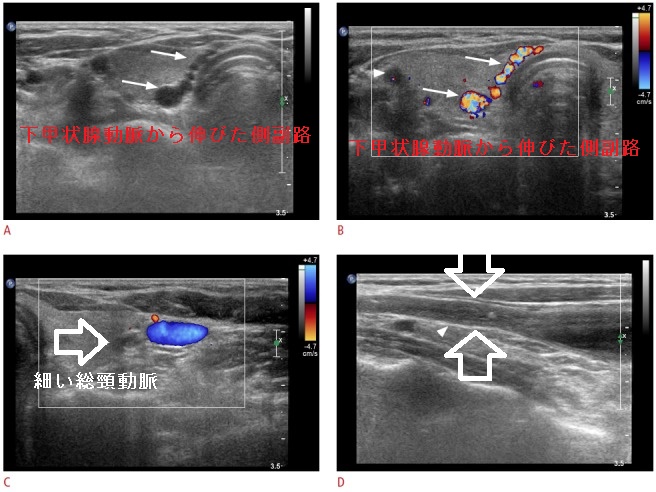

- 甲状腺超音波エコー検査の際に、①下甲状腺動脈から伸びた側副路、②壁肥厚と管腔内血流欠損を伴う狭小化した総頸動脈を認め、偶然、大動脈炎症候群(高安動脈炎)が見つかった。[Ultrasonography. 2014 Jul;33(3):222-5.]